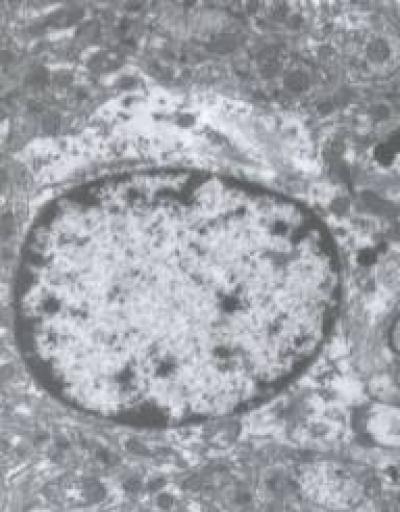

Aberrant Wnt signaling is possibly related to the pathological changes in Alzheimer's disease (AD). Axin and β-catenin protein is closely related to Wnt signaling. Zhou Hua and his team, Hubei University of Chinese Medicine, China confirmed that moxibustion or electroacupuncture, or both, at Baihui (GV20) and Shenshu (BL23) acupoints decreased axin protein expression, increased β-catenin protein expression, and alleviated neuronal cytoplasmic edema. These findings suggest that the mechanism underlying the neuroprotective effect of acupuncture in AD is associated with axin and β-catenin protein expression in the Wnt signal transduction pathway. Related results were published in Neural Regeneration Research (Vol. 9, No. 9, 2014).